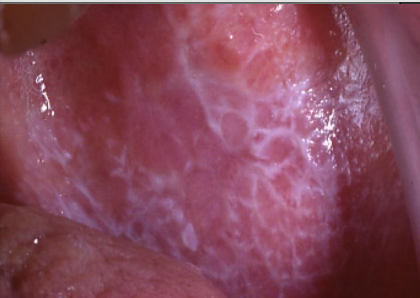

What is erosive lichen planus?

Not as common, painful, erythematous, bleeding

White lace-like striations (Wickham striae), maybe erythematous, bleeding

Buccal mucosa, gingiva, tongue, lip